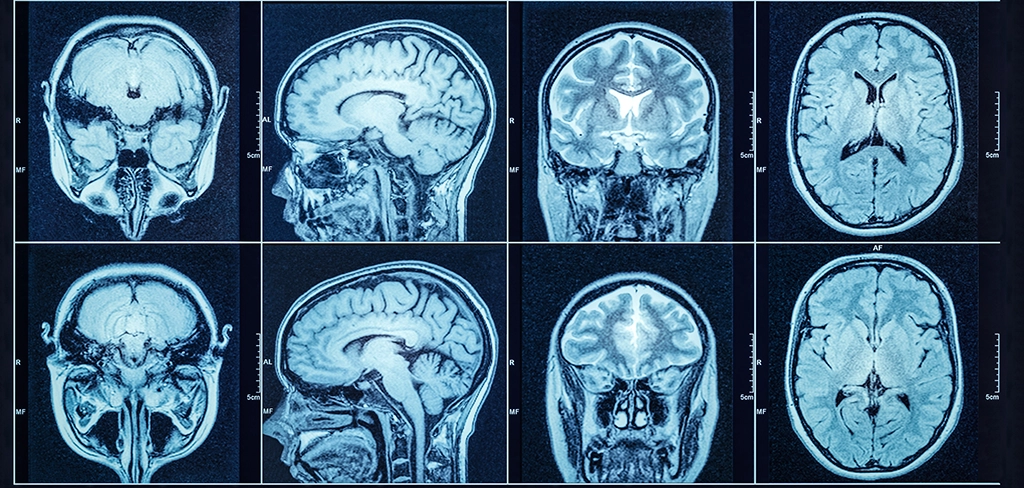

Terakhir, bintang utama hadir: MRI. Berbeda dengan dua teknologi sebelumnya, MRI menampilkan detail resolusi tinggi, bahkan hingga serat-serat halus pada pisang. Analogi ini memperlihatkan kemampuan MRI membaca jaringan lunak dengan sangat detail, sehingga mampu membedakan antara luka otot atau sekadar pegal biasa. Tak heran, MRI dikenal sebagai metode pencitraan yang paling mahal, tapi juga paling informatif.